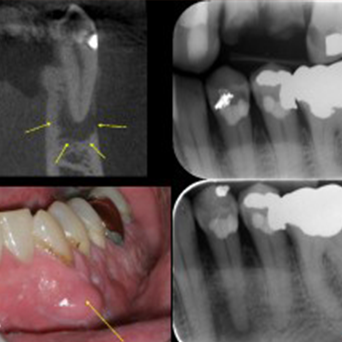

뿌리끝병소

치근 끝 부위에 염증이나 낭종이 생긴 상태

주요 증상

- 잇몸 부종

- 씹을 때 불편함

- 간헐적 통증